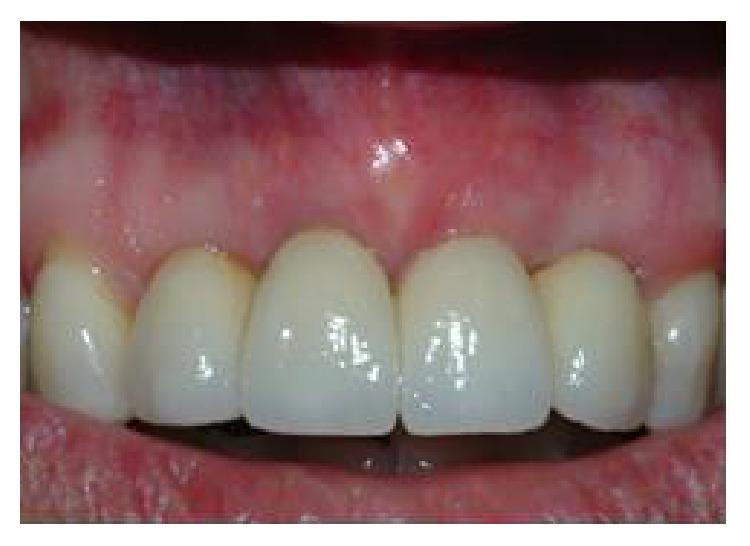

The functional and aesthetic restoration of teeth compromised due to aggressive periodontitis presents numerous challenges for the clinician. Horizontal bone loss and soft tissue destruction resulting from periodontitis can impede implant placement and the regeneration of an aesthetically pleasing gingival smile line, often requiring bone augmentation and mucogingival surgery, respectively. Conservative approaches to the treatment of aggressive periodontitis (i.e., treatments that use minimally invasive tools and techniques) have been purported to yield positive outcomes. Here, we report on the treatment and five-year follow-up of patient suffering from aggressive periodontitis using a minimally invasive surgical technique and implant system. By using the methods described herein, we were able to achieve the immediate aesthetic and functional restoration of the maxillary incisors in a case that would otherwise require bone augmentation and extensive mucogingival surgery. This technique represents a conservative and efficacious alternative to the aesthetic and functional replacement of teeth compromised due to aggressive periodontitis.

侵袭性牙周炎导致牙齿功能和美观受损,给临床医生带来诸多挑战。牙周炎引起的水平骨吸收和软组织破坏会妨碍种植体植入以及美观的牙龈微笑线的再生,通常分别需要进行骨增量和膜龈手术。据称,侵袭性牙周炎的保守治疗方法(即使用微创工具和技术的治疗方法)能产生积极效果。在此,我们报告了一名侵袭性牙周炎患者采用微创外科技术和种植系统的治疗及五年随访情况。通过使用本文所述方法,在原本需要骨增量和广泛膜龈手术的病例中,我们成功实现了上颌切牙的即刻美观和功能恢复。该技术是侵袭性牙周炎导致牙齿功能和美观受损时,一种保守且有效的替代治疗方法。